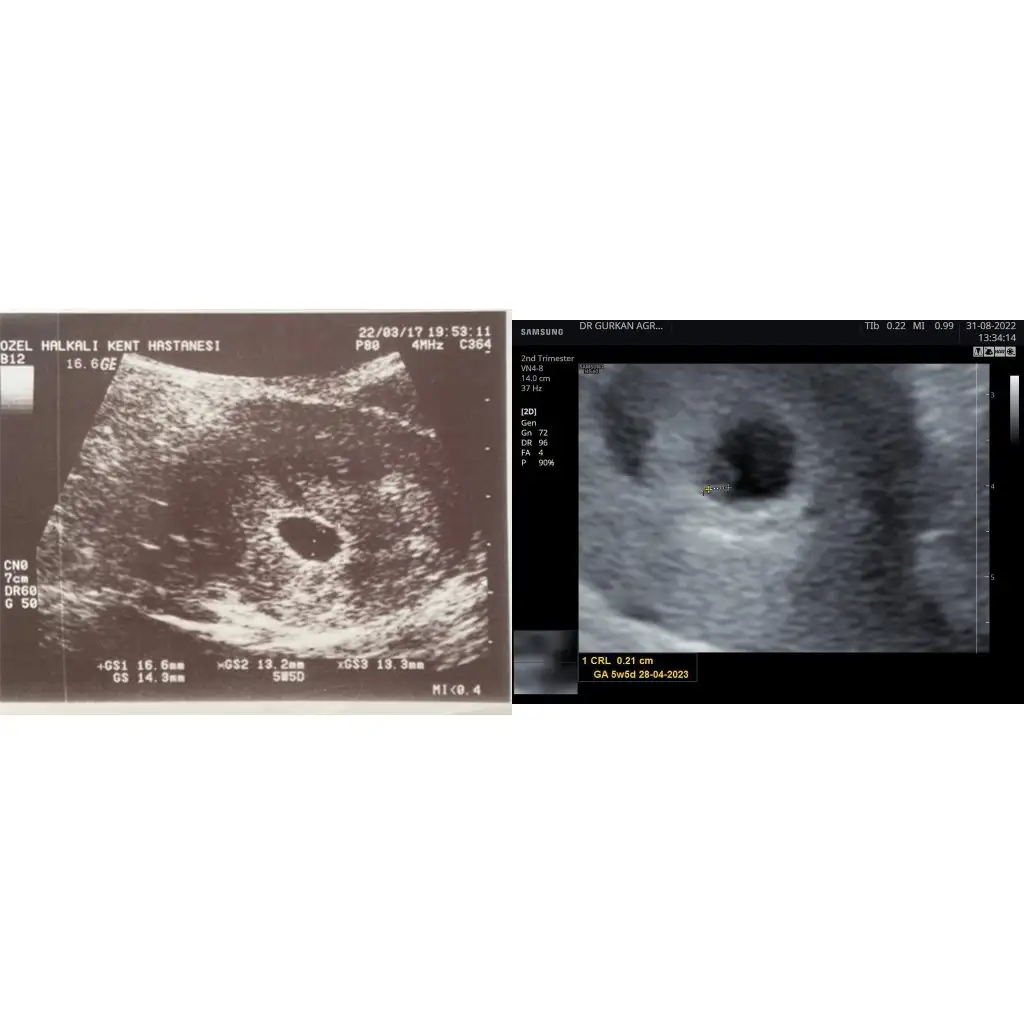

2017 doğumlu bir oğlum var onunla usg fotoğraflarına bakarken farkettim ki onda da ilk 5hafta 5 günlükken doktora gitmişim. Şimdi de öyle oldu ikisinde de usg de 5hafta 5 gün yzıyor😍 yan yana koyuyorum soldaki oğlumun ilk usg si sağdaki şuanki bebeğimin. Ramzi teorisine göre oğlumun ki tutuyor mu sizce. Şuan ki ne oluyor ozaman♥️